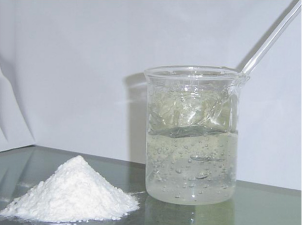

卡波姆为白色疏松状粉末

具有引湿性

遇水溶胀

在水中分散后呈酸性

被适量碱中和后

迅速溶胀为半透明高黏度凝胶或溶解为黏稠溶液

974P溶解示意图

而无机碱中和剂有氢氧化钠、氢氧化钾等

可将中和剂配成一定浓度的溶液

缓缓加人卡波姆溶胀液中

卡波姆水分散液的粘稠度会随着pH值的升高而逐渐升高

直至变为透明性凝胶(一般在pH值为6 -11时最稠)